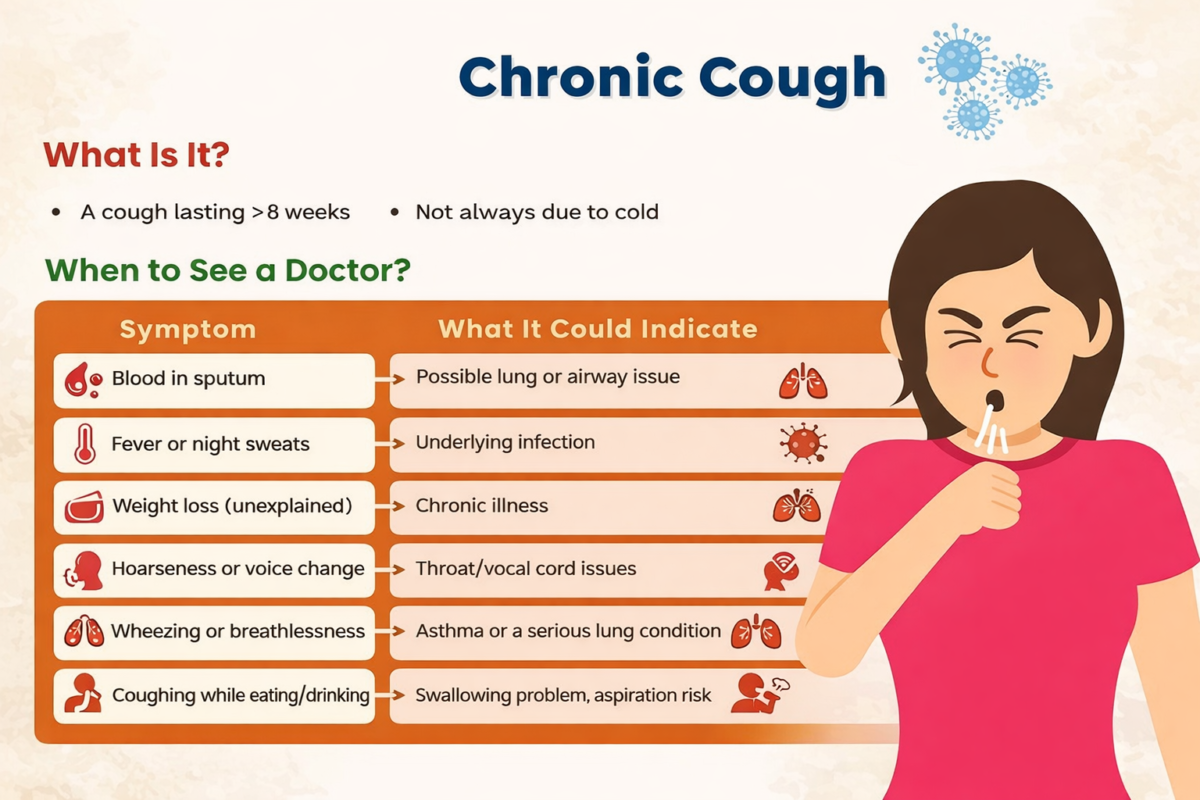

Persistent coughing or difficulty swallowing should also be treated as a warning sign. A persistent cough, hoarse voice, or chest pain could be a symptom of lung cancer or throat cancer. Difficulty swallowing food could be a symptom of cancer of the esophagus, throat, and other parts of the digestive tract. Change in bowel or bladder habits, such as constipation, diarrhea, or frequent urination, could be a symptom of cancer of the colon, rectum, or bladder.

It is extremely important to recognize when it is time to see a doctor for any of the possible cancer symptoms. This is because seeking early medical care for cancer symptoms can result in better treatment outcomes. In this case, it is recommended that if a person recognizes any unusual changes in their body, which persist for more than two or three weeks without a logical explanation, they should consider seeking medical advice.

In addition, if a person recognizes unusual changes such as unexpected weight loss, fatigue, pain, and any other unusual changes that do not improve even after receiving basic medical care, they should consider seeking medical care. This is because, unlike other health changes, cancer symptoms are normally persistent, progressive, and unexplained. In addition, it is imperative not to ignore any of the unusual changes recognized in the body, as cancer symptoms normally manifest themselves as unusual changes.

Another reason for seeking medical care for cancer symptoms is when a person recognizes any abnormal changes in their body, such as lumps, swelling, and thickening of any part of the body, especially in areas such as the breast, neck, and testicles. In addition, abnormal bleeding, such as blood in the stool, urine, and while coughing, as well as abnormal discharge, should never be ignored, as it can sometimes manifest itself as cancer.

Also, it is advisable to seek medical attention if you have long-lasting respiratory symptoms such as a persistent cough, hoarseness of the throat, and discomfort in the chest, especially if you are a smoker or have been exposed to harmful substances. Moreover, if you have a family history of cancer and have genetic risk factors, it is advisable to be even more careful and to regularly seek medical checkups and screenings even in the absence of symptoms.